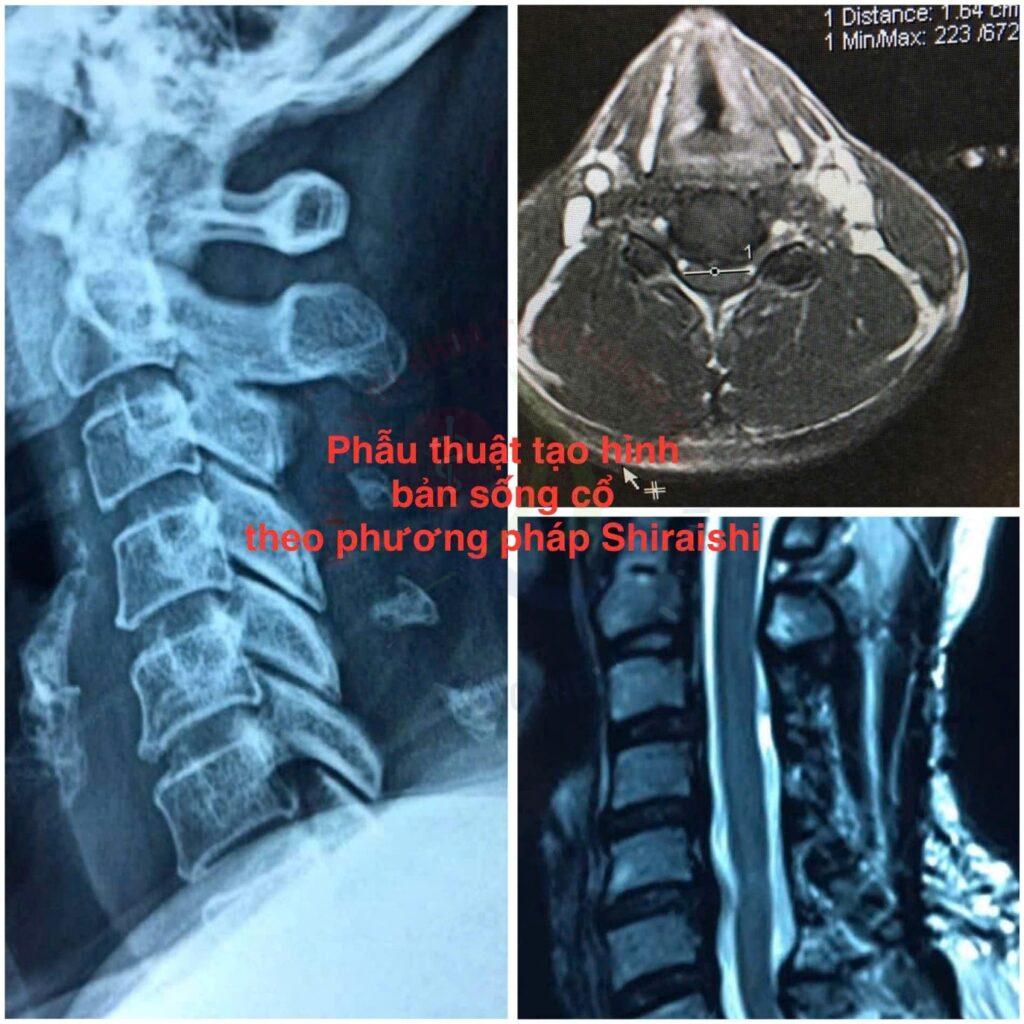

Cuối tháng 8 vừa qua, một bệnh nhân nam 54 tuổi, nhập viện trong tình trạng yếu tứ chi, hạn chế vận động, cầm nắm khó, tiểu khó. Hình ảnh MRI cho thấy, bệnh nhân bị hẹp ống sống cổ nặng C3C4 – C4C5 – C5C6, tổn thương tủy cổ C5 – C6. Ê kíp bác sĩ Khoa Ngoại Cột sống, Bệnh viện Đa khoa Khánh Hòa đã chỉ định phẫu thuật tạo hình bản sống cổ theo phương pháp Shiraishi.

Đây là một kỹ thuật hiện đại giúp mở rộng ống sống, bảo tồn nơi bám của các cơ vùng sau cổ. Nhờ đó, các bác sĩ giải phóng hoàn toàn chèn ép tủy cổ, giữ lại cấu trúc giải phẫu và chức năng vận động vùng cổ sau phẫu thuật. Ca phẫu thuật thành công giúp phục hồi vận động trở lại cho bệnh nhân. Ông vui mừng chia sẻ: “Hiện tại, tôi đã hồi phục vận động tay chân, đi lại được, tiểu tiện bình thường. Cơ lực tay và cảm giác tứ chi hồi phục tốt lắm, tôi cảm ơn bác sĩ phẫu thuật cho mình”.